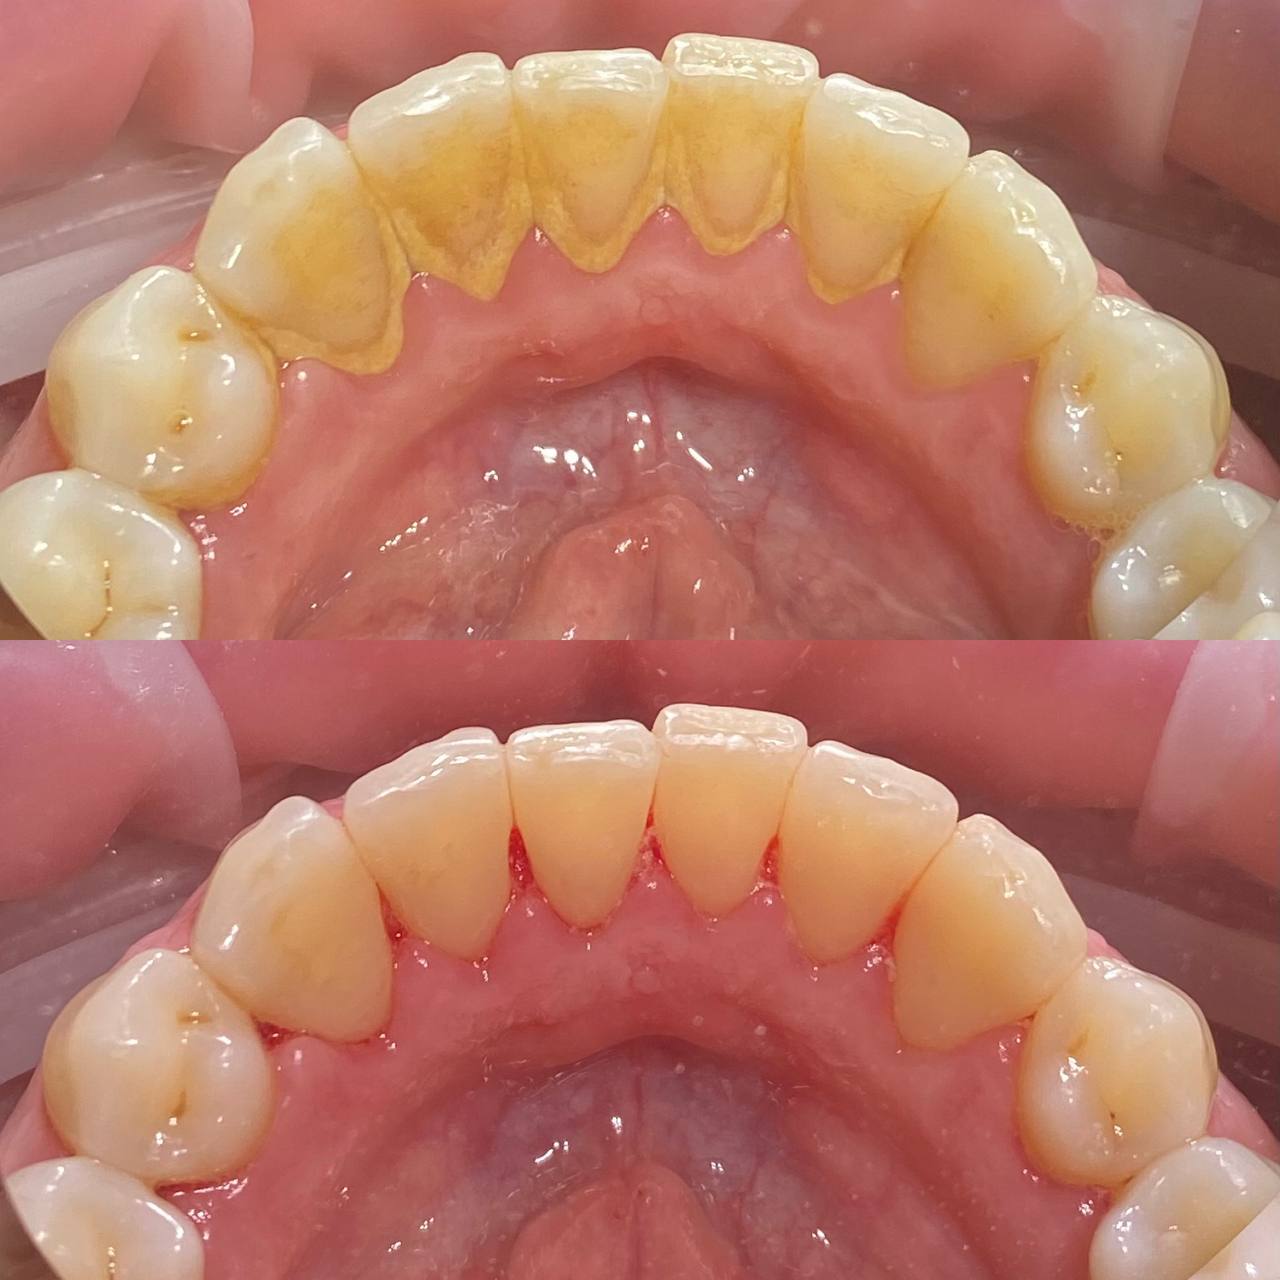

Даже если вы хорошо чистите зубы дома, на зубах со временем скапливается налет. А также на зубах есть труднодоступные места, которое вы не прочищаете. Поэтому нужно приходить на профгигиену в клинику не реже 1 раза в 6 месяцев. Очищение налета, удаление зубного камня, укрепление эмали — все это профессиональная гигиена. На сегодня это лучший способ защитить зубы от кариеса и сохранить десны здоровыми.

Процесс включает несколько этапов:

• Удаление зубного камня с помощью ультразвука;

• Очистка труднодоступных участков с использованием порошкового оборудования Air Flow;

• Полировка зубов специальными пастами, придающими эмали гладкость и блеск;

• Завершение процедуры нанесением реминерализующего состава для укрепления зубов.

• обучение домашней гигиене и подбор средств.